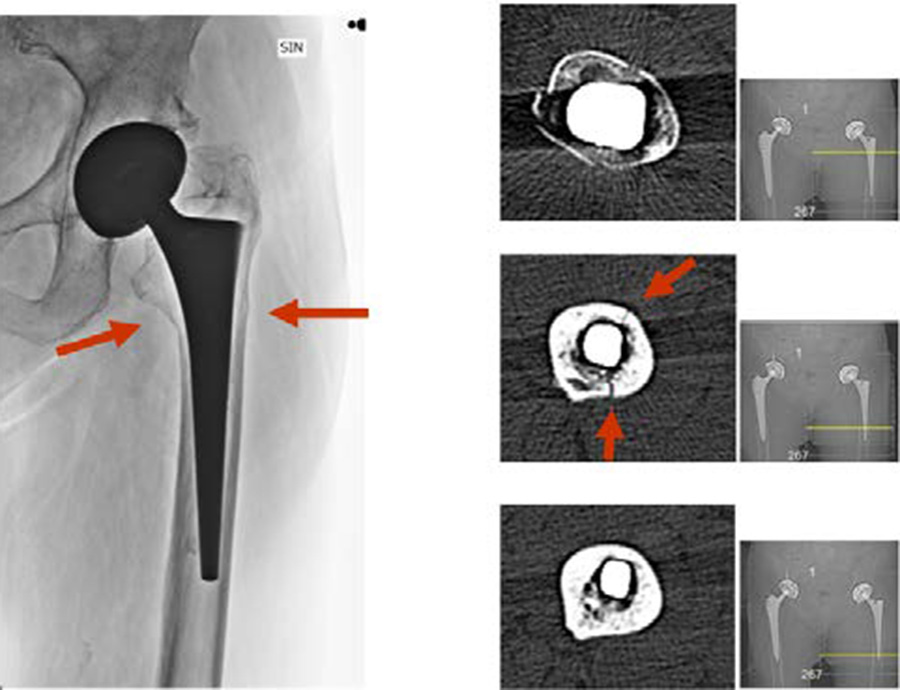

Assessing the stem

As has been discussed in Part 2 of this series, one essential diagnosis in treating PPFF is to determine whether a stem is loose. This question often translates into, "Is the fracture Vancouver type B1 or type B2/B3?" To achieve a reasonably accurate diagnosis, it is essential to take high-quality x-rays in at least two planes at the pelvis level to determine if the stem is loose or stable. Radiolucent lines detected around the prosthesis or cement is an indication of osteolysis, stem loosening, or stem subsidence [1]. A computed tomographic (CT) scan is helpful in showing fracture pattern, extension of osteolysis, and even implant fixation. If the imaging does not offer a conclusive diagnosis of a stable stem, and during surgery implant stability is still doubtful, then a stem revision should be carried out.